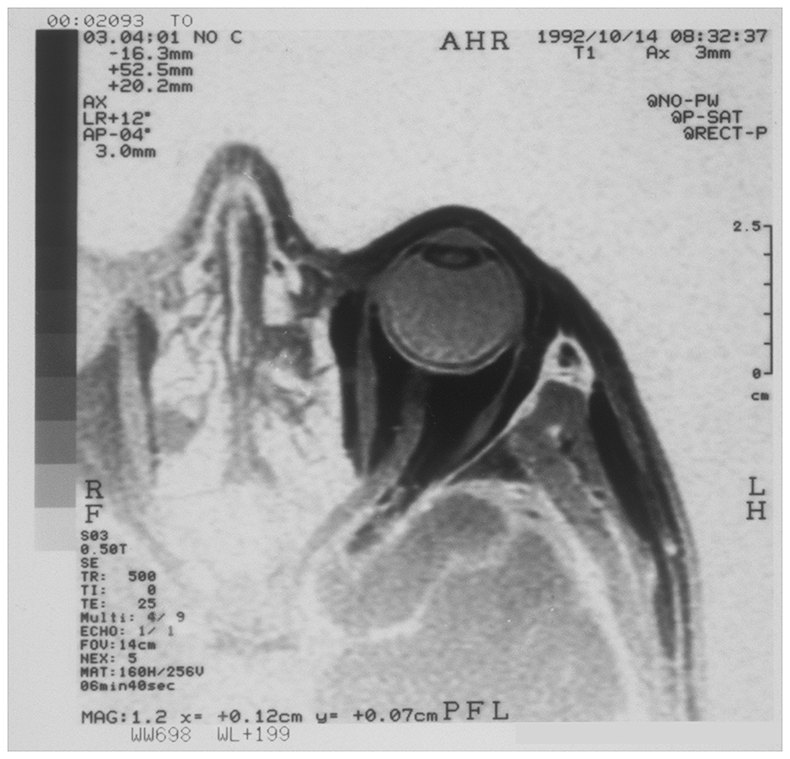

MRI scan of the eye

Da Vinci located the soul at the junction of the optic nerves, thereby linking light, vision and truth and a series of five eye images related to this.

Print of section through the eye.